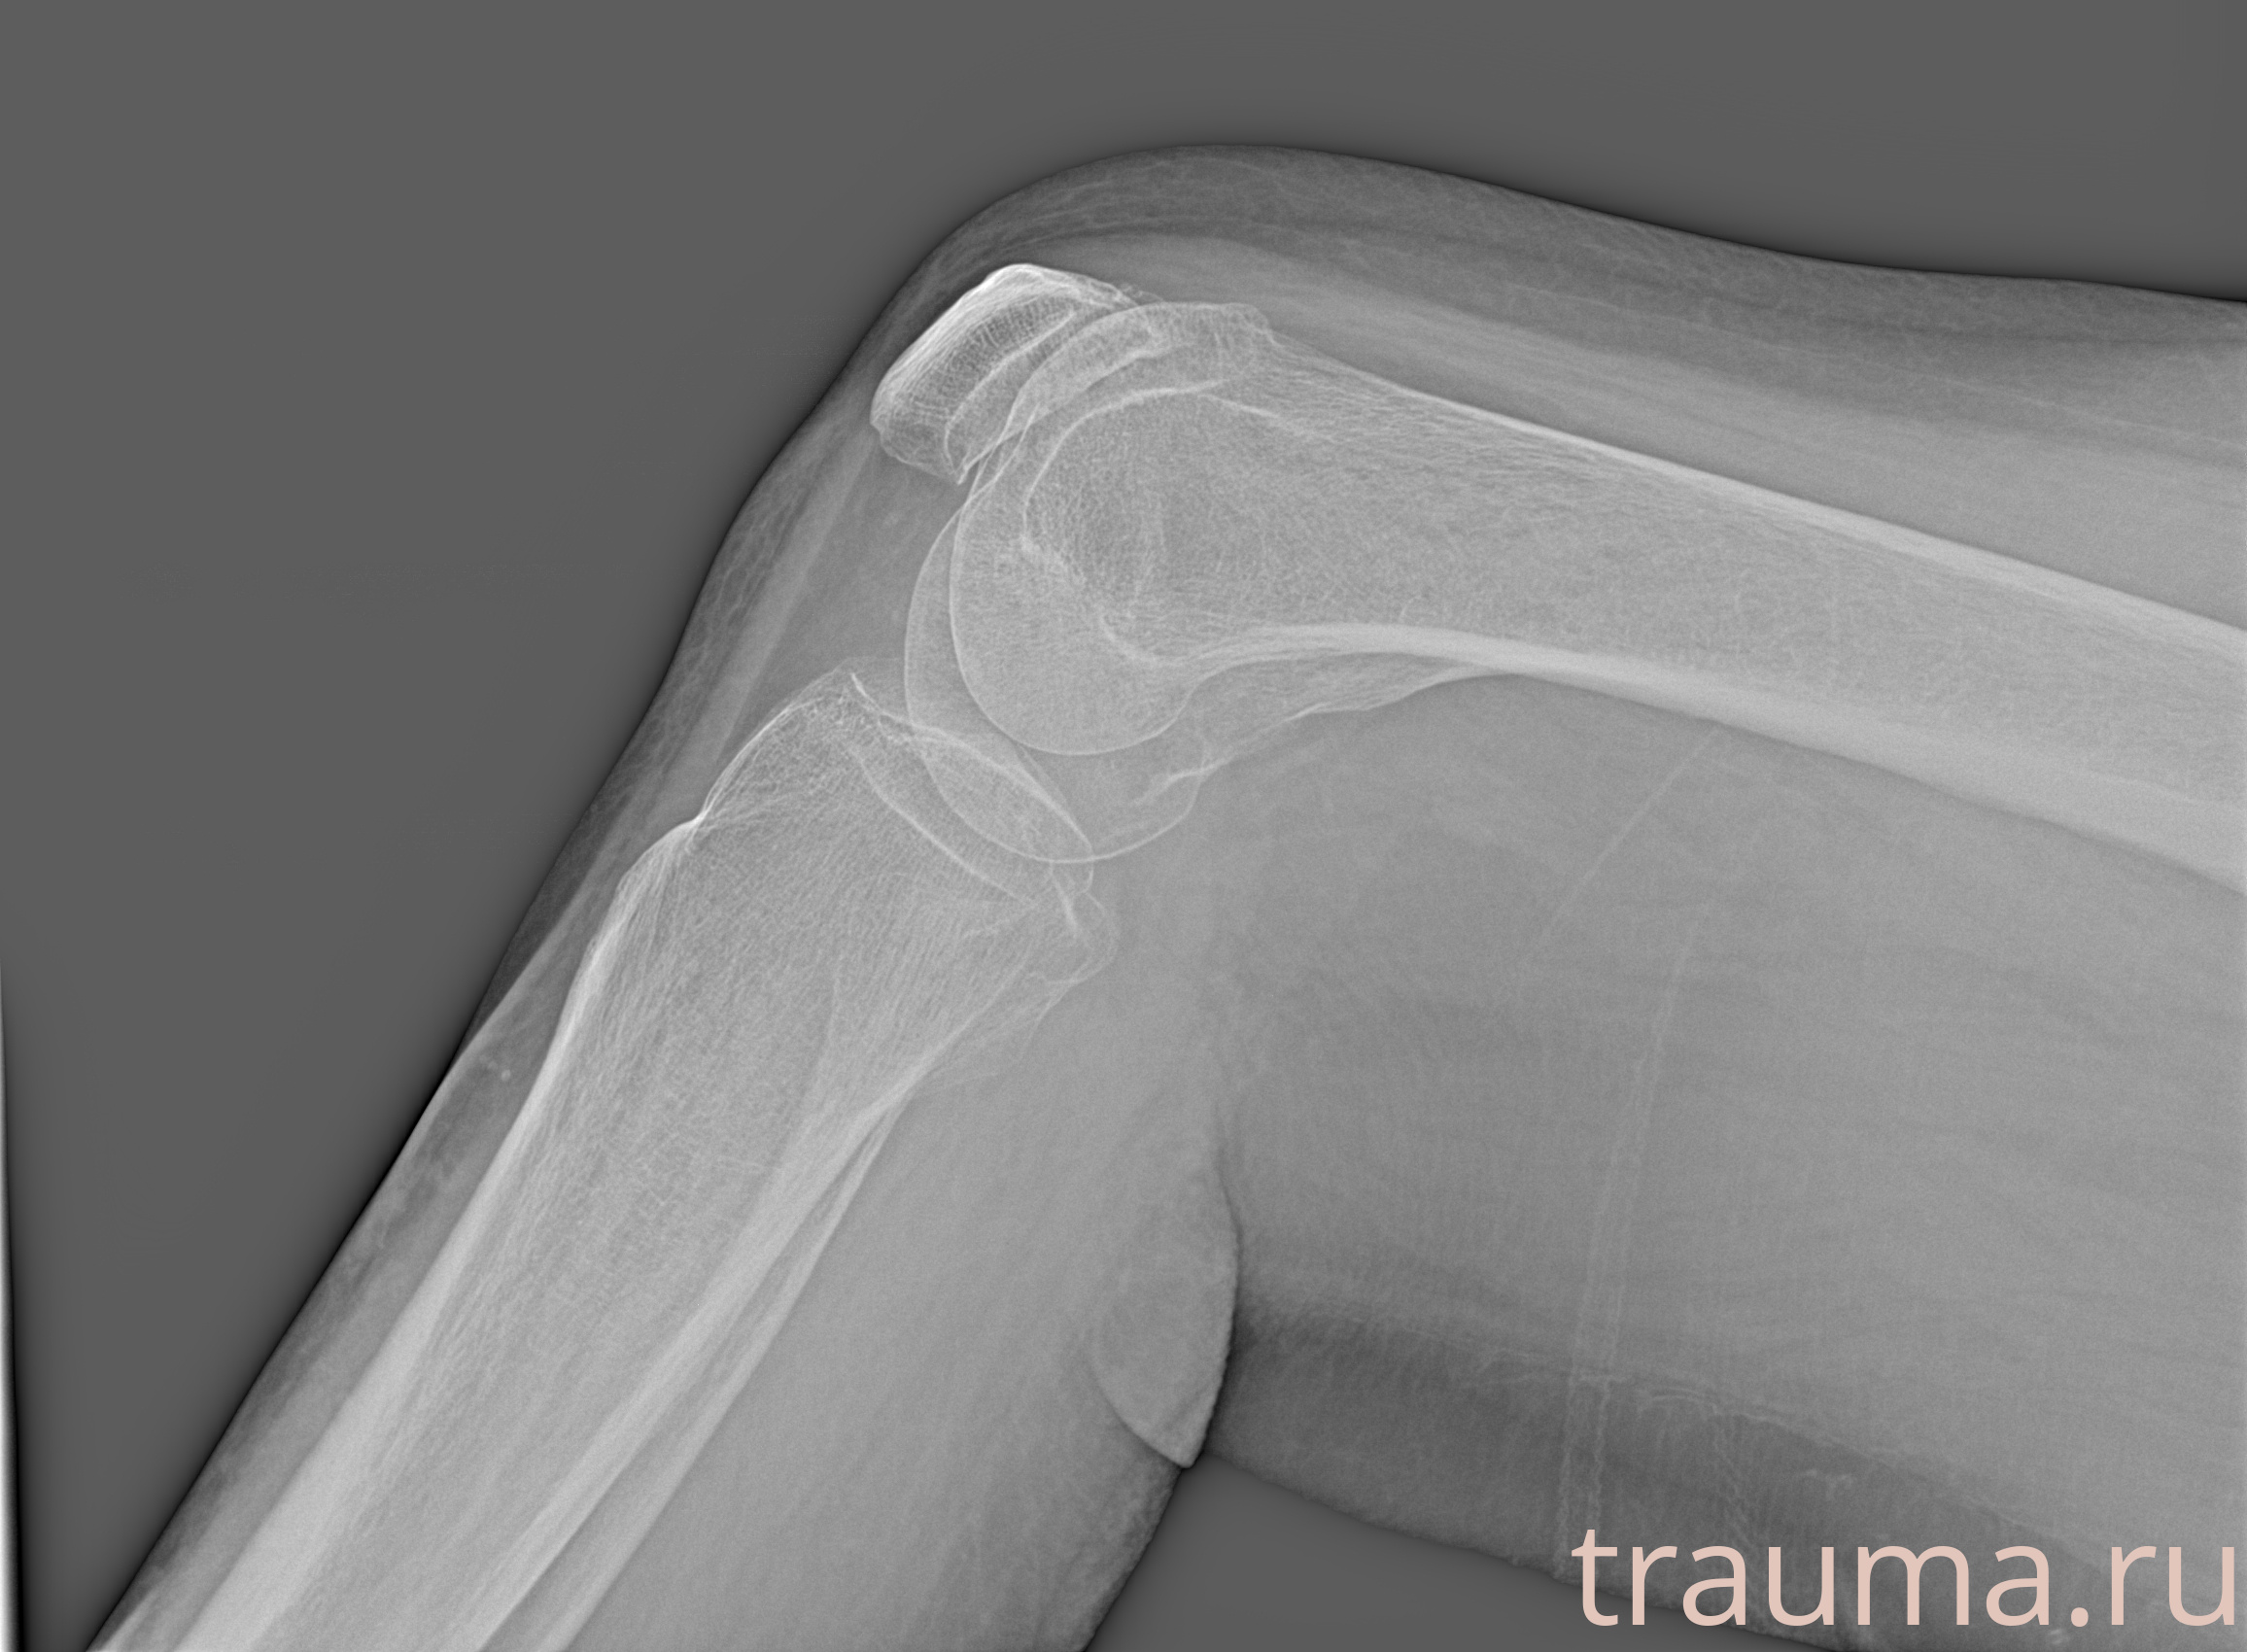

Рентгенограммы

Рентген на дому: по вашему адресу приезжает врач-рентгенолог, травматолог-ортопед с мобильным рентгеновским аппаратом, проводит диагностику травмы или заболевания, делает необходимые рентгенограммы, дает рекомендации по дальнейшему лечению. Получить качественные снимки в домашних условиях возможно благодаря уникальной методике, разработанной МосРентген Центром для института  Склифосовского